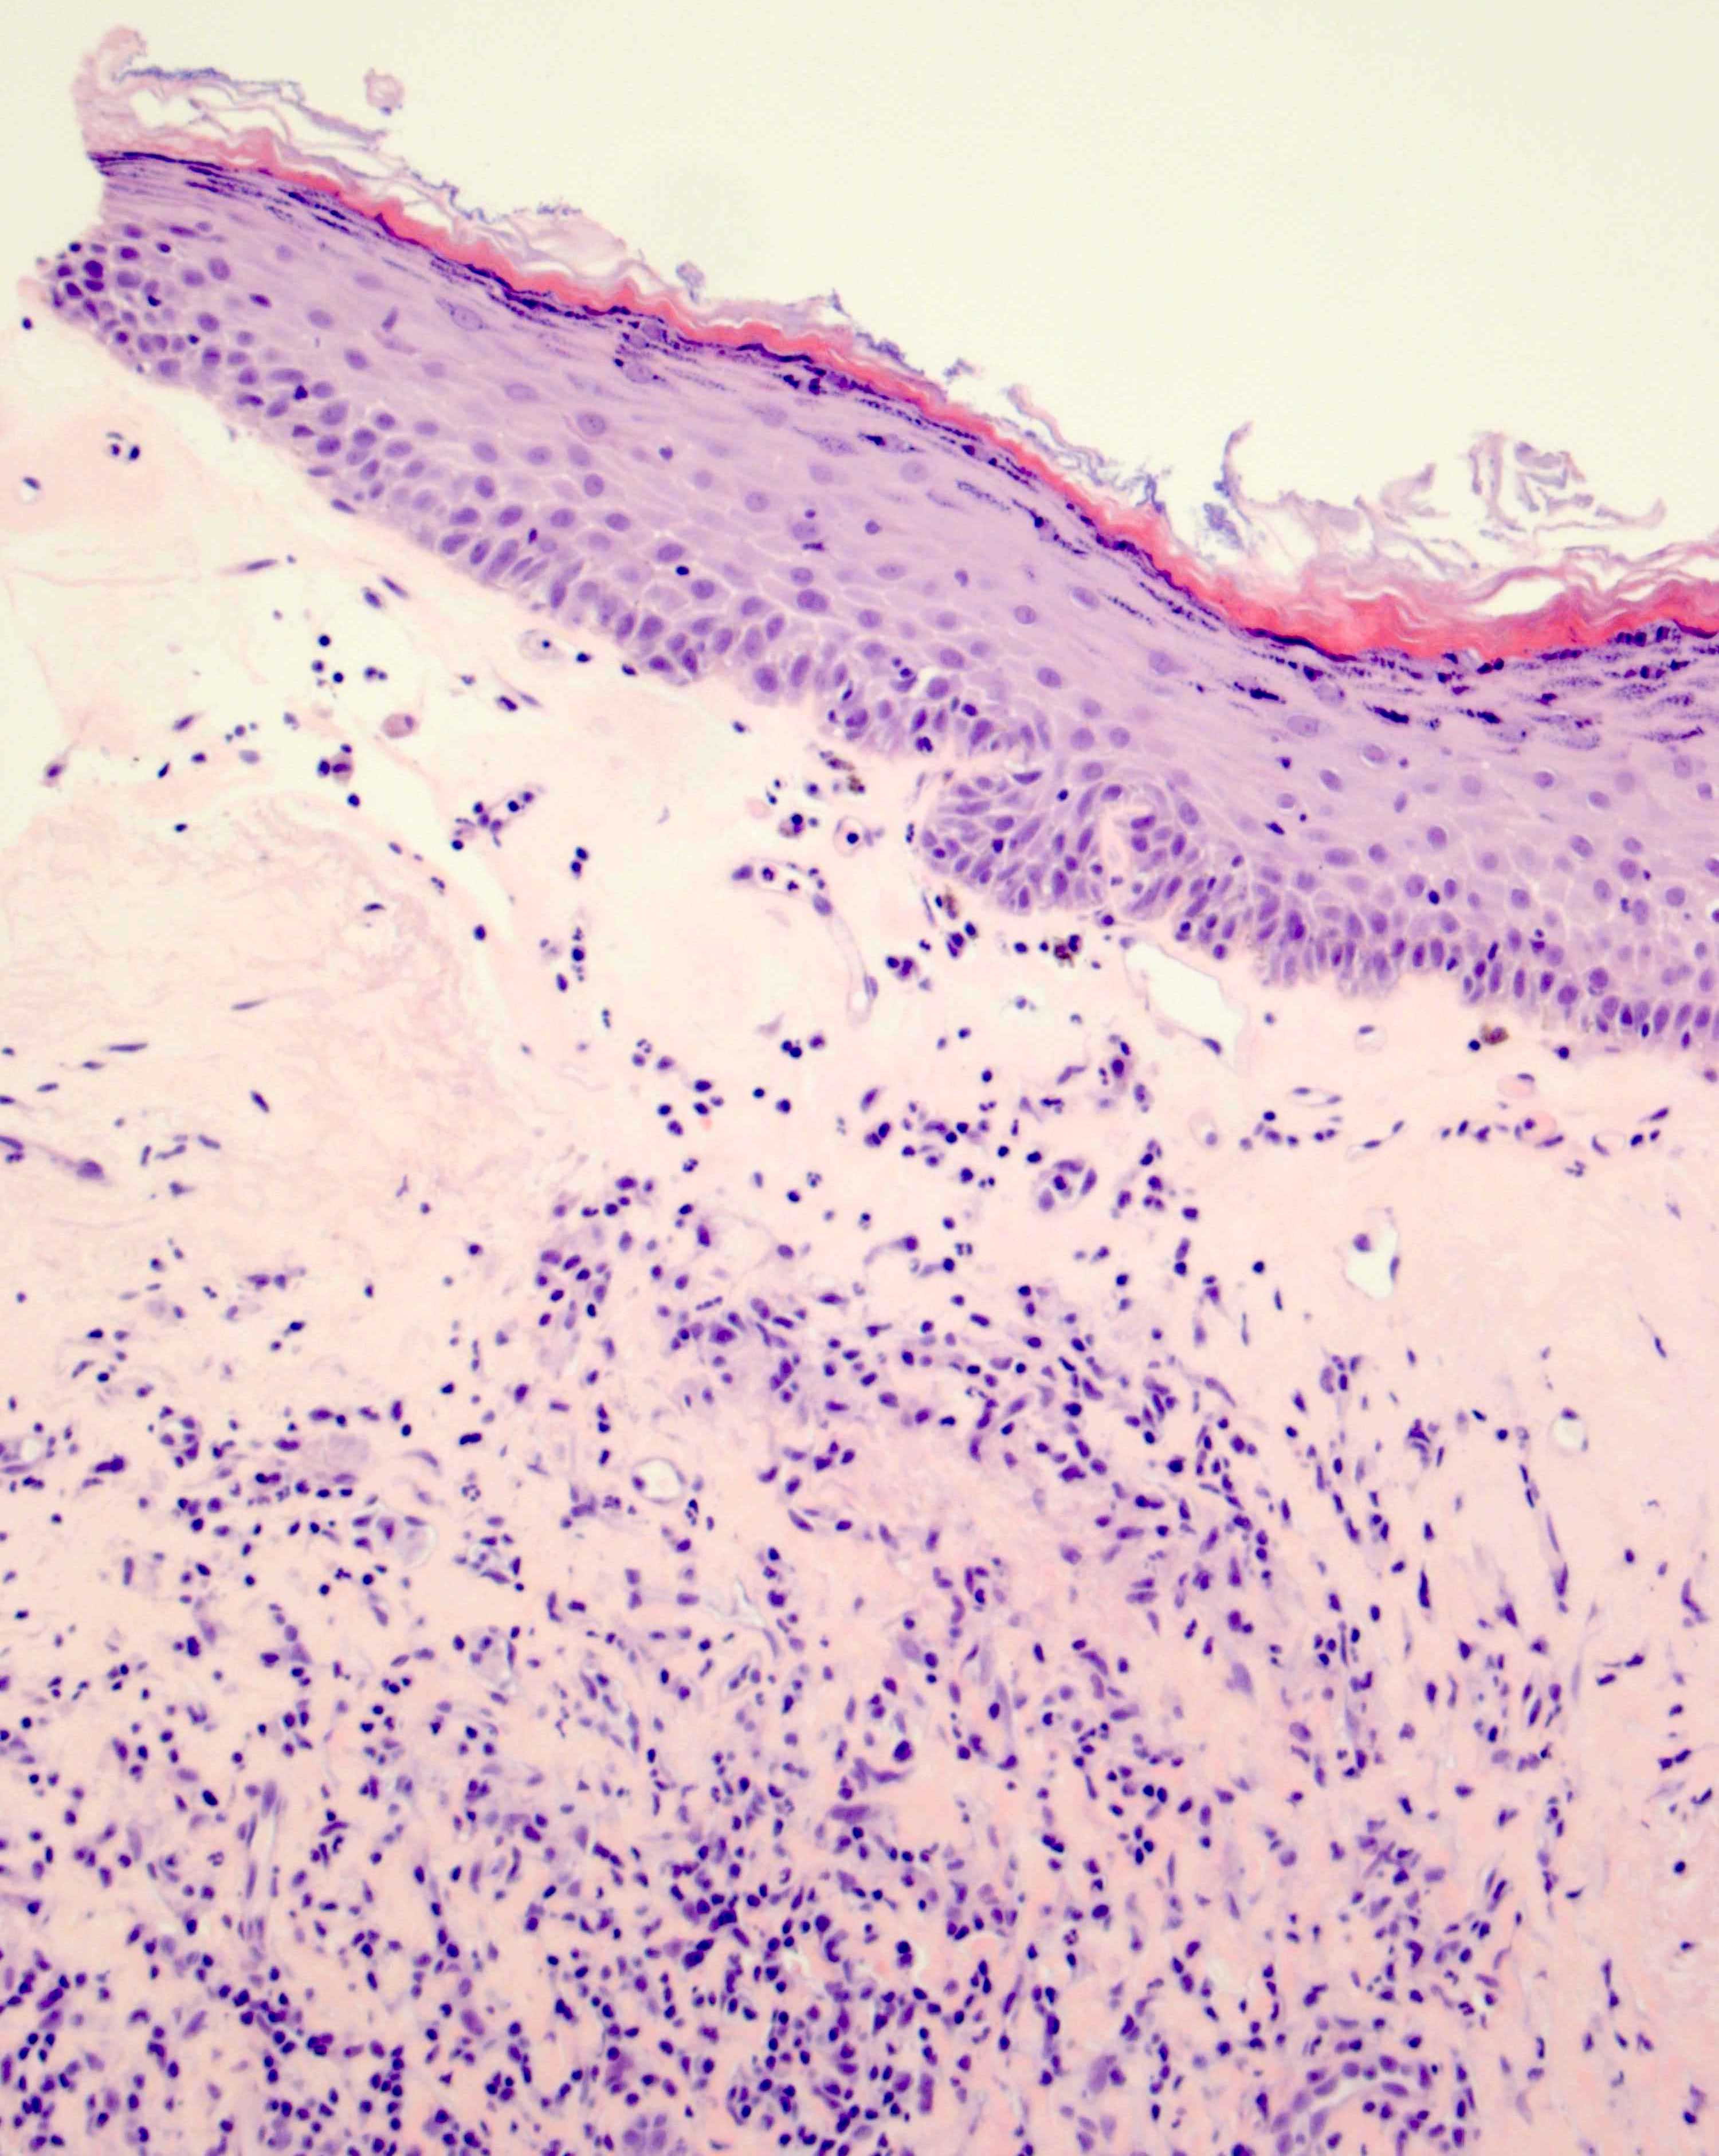

- Vacuolar interface reaction pattern in conjunction with dermal sclerosis (homogenized and hyalinized eosinophilic collagen bundles) of any thickness intervening between inflammatory infiltrate and epithelium or vessel walls (Mod Pathol 1998;11:844)

- Early lesions show only the inflammation and no or minimal fibrosis (inflammatory phase); the histopathological findings at this stage of disease development are not diagnostic

- Severe hyperkeratosis; thin epidermis, loss of rete pegs, basal cell degeneration, homogenized band of dense fibrosis at papillary dermis, upper dermal edema, band-like chronic inflammation

- Early dermal changes are homogenized collagen and wide ectatic capillaries in dermal papillae immediately beneath basement membrane

- Superficial dermal collagen may be wire-like with lymphocyte entrapment (J Cutan Pathol 2015;42:510)

- Lymphocytic infiltrate can be sparse or dense, lichenoid or interstitial with epidermal lymphocyte exocytosis

Microscopic (histologic) images